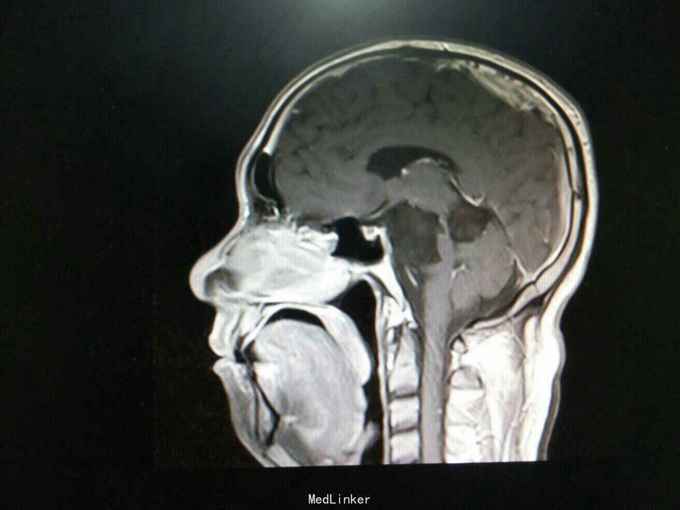

查体:生命体征平稳。神经系统检查:右侧眼睑下垂,左侧眼睑无下垂。肌力 右侧肢体肌力5-级,左侧肢体肌力正常。肌张力: 右上肢肌张力正常,右下肢肌张力正常;左上肢肌张力正常,左下肢肌张力正常。肌营养检查:四肢肌肉无萎缩。共济与平衡检查:正常。外院颅脑CT示右侧桥脑小脑角团片囊性低密度区,性质待定,蝶窦右后方局部骨质缺损代之稍低密度软组织肿块,考虑原肿瘤复发,颅骨呈术后改变,颅脑CT增强示颅内占位性病变(表皮样囊肿?)。入院后行颅脑MRI检查提示: 右侧颞骨岩尖-脚间池-右侧环池-右侧桥小脑角池见片状异常信号影,边界清,形态不规则,呈匍匐状分布,冠状位范围约47mm×29mm。相应右侧颞、脑干明显受压,脑干向左移位。第三脑室略向左移位。右侧额骨、颞骨骨皮质欠连续,呈术后改变。 考虑右侧颞骨岩尖-脚间池-右侧环池-右侧桥小脑角池表皮样囊肿。 右侧颅骨呈术后改变。